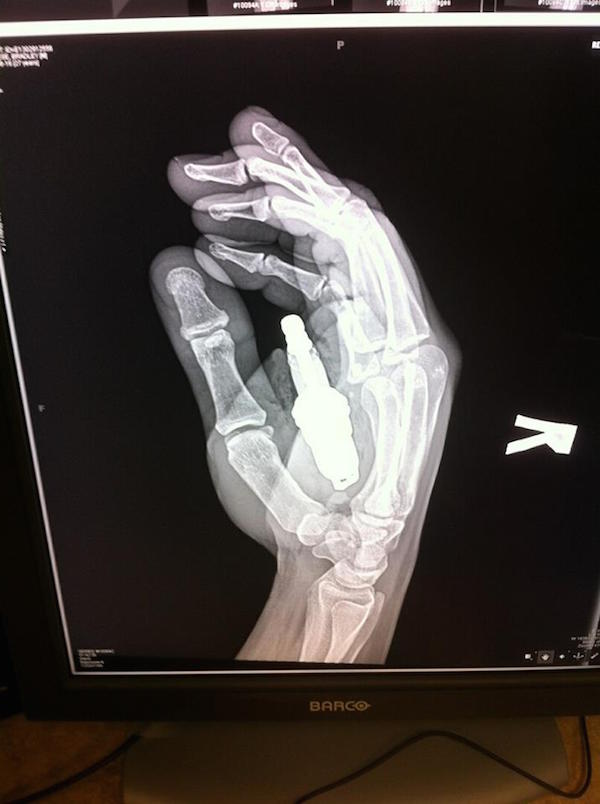

This guy, who left the hospital with the greatest x-ray of all time. Yes, that’s a spark plug lodged inside his palm. Evidently, the involved parties constructed a makeshift launching apparatus from 3/4-inch metal tubing and an air compressor. It backfired. One very messy ride to the emergency room later, the plug was extracted. Didn’t even need surgery. Hero.